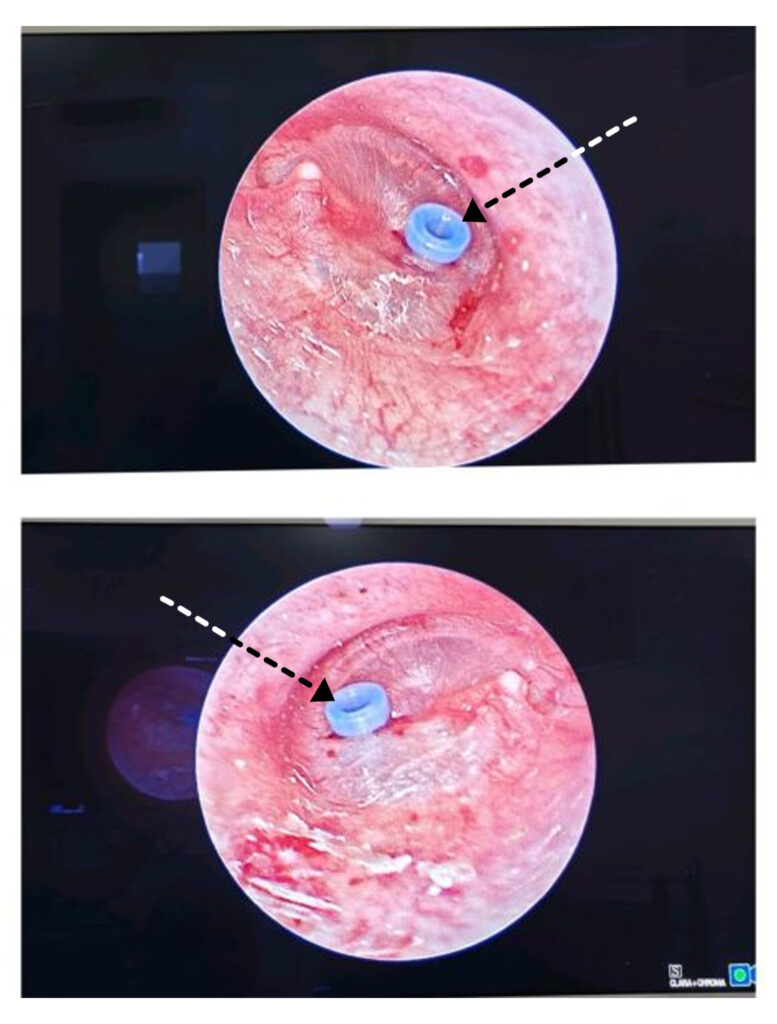

Myringotomy and Grommet

Tympanic Membrane Perforation